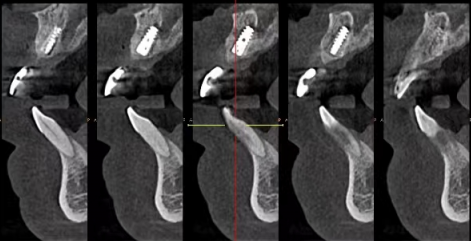

医生团队是医院的核心竞争力之一。以牙齿矫正医生为例,他们不仅具备扎实的理论知识,还在实践中积累了大量的成功实例。在技术优势上,维乐口腔不断引进精良的口腔医疗设备,如口腔CT、数字化正畸系统等,提高了诊断和治疗的正确性和效率。从口碑方面来看,在各大医疗评价平台上,都能看到患者对北京维乐口腔的高度评价,称赞其技术好、服务优。